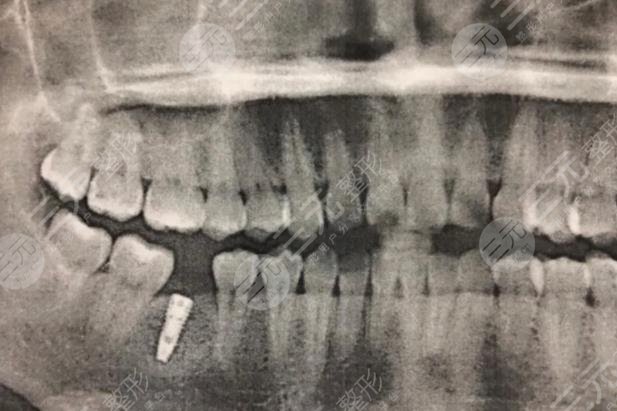

于是在朋友的陪伴下,我来到医院,医生亲切的接待了我,医生判断我的牙齿已经完全龋坏,做修复已然不可能,他建议我拿掉,然后做种植牙,种植牙降低风险系数高,使用寿命长,而且**较为的高。此前我比较担心疼痛,但医生给我解释到种植牙所用的是局部mz,完全没有疼痛感,其疼痛程度低于拔智齿。在比较详细了解相关信息以后,我就决定在这家医院做种植牙,而事实证明,我的决定是较为正确的,当天我就做了拔牙,然后医生给我定制了专门的牙冠以及种植体。

过一段时间以后就进行种植修复,诚如医生所言,整个过程没有明X的痛感,回去以后有麻麻的感觉。不过好在可以忍受。做完以后,我感觉吃什么都香了,对此我较为的满意,也建议大家牙齿有问题的话,应该尽快去处理避免错过好的时间。